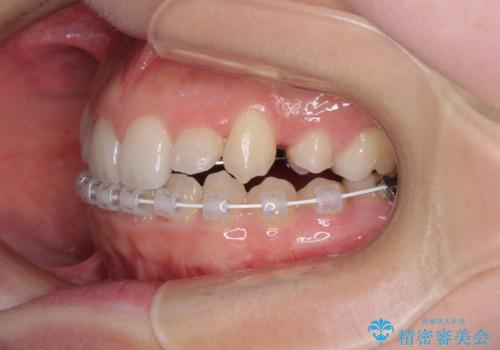

目立つ八重歯を目立たない装置で ハーフリンガルによる抜歯矯正

- 矯正装置

- ハーフリンガル

- 前歯のデコボコと八重歯を気にして来院された患者様です。

目立たない装置を希望されたので、上顎が裏側装置のハーフリンガルを選択し、左右上顎小臼歯1本ずつを抜歯して、矯正治療を行うこととしました。

治療期間の目安は2年半~3年間でしたが、予定通り治療が進み、2年半弱で終えることができました。

歯列はきれいに整い、治療期間も予定通りであり、患者様には大変満足していただきました。